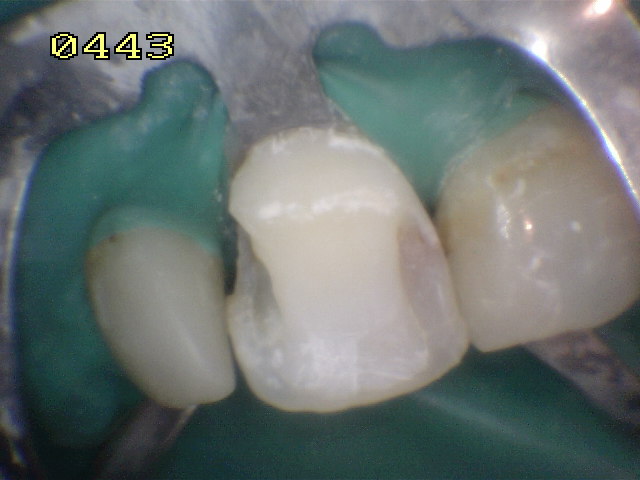

Se elimina el material y

tejido cariado, con un rebaje de la cara vestibular |

| El rebaje

del esmalte vestibular se hizo en la forma del esquema, es

importante dejar esmalte para su posterior grabado con acido

ortofosfórico al 37% |